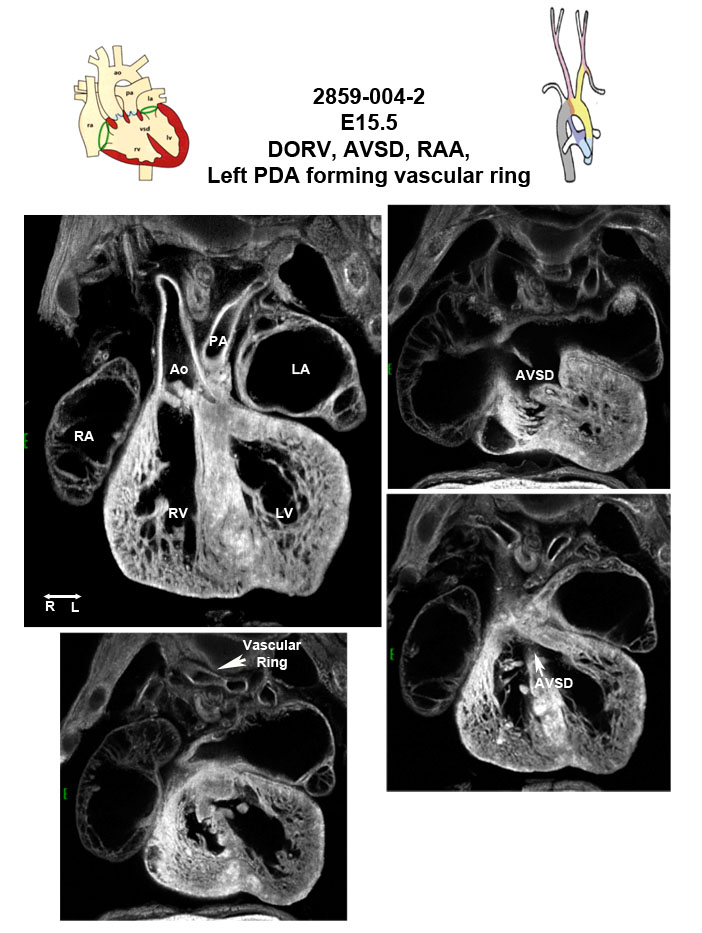

Caption EFIC Summary

Copyright This image is from the Laboratory of Dr. Cecilia Lo, a member of the Cardiovascular Development Consortium (CvDC), Bench to Bassinet (B2B) program of the National Heart Lung and Blood Institute (NHLBI), and is displayed with the permission of the authors. J:175213

Pigvb2b2859Clo phosphatidylinositol glycan anchor biosynthesis, class V; Bench to Bassinet Program (B2B/CVDC), mutation 2859 Cecilia Lo

Pigvb2b2859Clo/Pigvb2b2859Clo C57BL/6J-Pigvb2b2859Clo